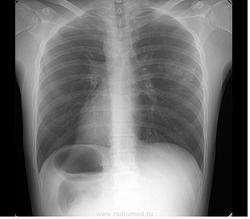

Пол пациента: Мужской пол Тип патологии: Другое Область исследования: Грудная клетка и верхние дыхательные пути Методы исследования: Другие Ж, 1976г. М, 1980 Скорее всего оба случая будут пропущены через туб. диспансер. Хотелось бы услышать ваши предварительные заключения) https://radiomed.ru/sites/default/files/styles/case_slider_image/public/user/5536/klementmd_82009_1.jpg?itok=rsgLS6s_ https://radiomed.ru/sites/default/files/styles/case_slider_image/public/user/5536/klementmd_82010_1.jpg?itok=1UPMmGH6 https://radiomed.ru/sites/default/files/styles/case_slider_image/public/user/5536/klementmd_82008_1.jpg?itok=wyVmKRJh ID:21496 Втр, 29/05/2012 - 22:06 #1 Катенёв Валенти... Не на сайте Был на сайте: 7 лет 3 недели назад Зарегистрирован: 22.03.2008 - 22:15 Публикации: 54876 Если Ж, последние три снимка, то необходима правая боковая томография в срезах 5,7,9 см. Втр, 29/05/2012 - 22:08 #2 Mitkampfer Не на сайте Был на сайте: 11 лет 1 месяц назад Зарегистрирован: 27.07.2010 - 07:43 Публикации: 1454 Ж. - первый снимок. Томография выполняется в тубдиспансере. Не ограничивайте свою мысль Живешь пока учишьсяEcrasez l’infame Втр, 29/05/2012 - 22:09 #3 Катенёв Валенти... Не на сайте Был на сайте: 7 лет 3 недели назад Зарегистрирован: 22.03.2008 - 22:15 Публикации: 54876 Линейная томография выполняется только в туб диспансере? Втр, 29/05/2012 - 22:10 #4 Mitkampfer Не на сайте Был на сайте: 11 лет 1 месяц назад Зарегистрирован: 27.07.2010 - 07:43 Публикации: 1454 ну у нас только цифровой флюорограф на станции) На дальнейшее дообследование отправляем в наш тубдиспансер. Не ограничивайте свою мысль Живешь пока учишьсяEcrasez l’infame Втр, 29/05/2012 - 22:11 #5 Катенёв Валенти... Не на сайте Был на сайте: 7 лет 3 недели назад Зарегистрирован: 22.03.2008 - 22:15 Публикации: 54876 А. что за "станция"? Втр, 29/05/2012 - 22:12 #6 Mitkampfer Не на сайте Был на сайте: 11 лет 1 месяц назад Зарегистрирован: 27.07.2010 - 07:43 Публикации: 1454 флюоростанция Не ограничивайте свою мысль Живешь пока учишьсяEcrasez l’infame Втр, 29/05/2012 - 22:19 #7 Катенёв Валенти... Не на сайте Был на сайте: 7 лет 3 недели назад Зарегистрирован: 22.03.2008 - 22:15 Публикации: 54876 Понятно. И, Вы работаете только на флюоростанции, или еще в рентгенодиагностике? Втр, 29/05/2012 - 22:22 #8 Mitkampfer Не на сайте Был на сайте: 11 лет 1 месяц назад Зарегистрирован: 27.07.2010 - 07:43 Публикации: 1454 На флюоростанции я совмещаю. но мы отвлеклись от темы) Не ограничивайте свою мысль Живешь пока учишьсяEcrasez l’infame Втр, 29/05/2012 - 22:24 #9 Катенёв Валенти... Не на сайте Был на сайте: 7 лет 3 недели назад Зарегистрирован: 22.03.2008 - 22:15 Публикации: 54876 Флюорограмма есть, патология есть, слово за томографией (в рентгеновском векторе). Втр, 29/05/2012 - 22:32 #10 Nikolas Не на сайте Был на сайте: 2 месяцев 9 часов назад Зарегистрирован: 21.12.2010 - 20:37 Публикации: 4559 случайные? Втр, 29/05/2012 - 22:42 #11 И.Бондаренко Не на сайте Был на сайте: 2 дня 6 часов назад Зарегистрирован: 13.09.2011 - 22:55 Публикации: 9206 В первом случае может что-то похуже выскочит. Во втором, в ПТД, возможно и пневмония. Ср, 30/05/2012 - 06:50 #12 Vikkur Не на сайте Был на сайте: 4 года 8 месяцев назад Зарегистрирован: 24.09.2009 - 14:34 Публикации: 1749 Ж архив, может и пост. измен, М в ПТД Виктор. Ср, 30/05/2012 - 13:20 #13 stovbav Не на сайте Был на сайте: 2 года 2 месяцев назад Зарегистрирован: 20.12.2009 - 17:28 Публикации: 7066 У Ж еще и 7-8-е ребра справа сломаны, причем - не очень давно)))) Болезни ног: виды, симптомы, причины, профилактика и лечение Ср, 30/05/2012 - 19:23 #14 Вылегжанина Юли... Не на сайте Был на сайте: 11 лет 5 месяцев назад Зарегистрирован: 15.05.2012 - 22:09 Публикации: 55 томография и направление в туб диспансер ,но там скорее всего поставят пневмонию и контроль после лечения Вылегжанина Юлия Ср, 30/05/2012 - 20:05 #15 Nikolas Не на сайте Был на сайте: 2 месяцев 9 часов назад Зарегистрирован: 21.12.2010 - 20:37 Публикации: 4559 комментарий, но не уверен в получении конечного результата, чтобы проверить правильность высказанных суждений. Ср, 30/05/2012 - 21:26 #16 Mitkampfer Не на сайте Был на сайте: 11 лет 1 месяц назад Зарегистрирован: 27.07.2010 - 07:43 Публикации: 1454 обоих направил в тубдиспансер результат должен быть. У Ж. плохой анамнез - наркомания, состояла на учете в ПТД какое то время, тбс не обнаружилось. У М. - нет жалоб. Не ограничивайте свою мысль Живешь пока учишьсяEcrasez l’infame Ср, 30/05/2012 - 21:43 #17 Mitkampfer Не на сайте Был на сайте: 11 лет 1 месяц назад Зарегистрирован: 27.07.2010 - 07:43 Публикации: 1454 stovbav wrote: У Ж еще и 7-8-е ребра справа сломаны, причем - не очень давно)))) согласен) +9 Не ограничивайте свою мысль Живешь пока учишьсяEcrasez l’infame

Ж. - первый снимок. Томография выполняется в тубдиспансере.

Флюорограмма есть, патология есть, слово за томографией (в рентгеновском векторе).

В первом случае может что-то похуже выскочит. Во втором, в ПТД, возможно и пневмония.

Ж архив, может и пост. измен, М в ПТД

У Ж еще и 7-8-е ребра справа сломаны, причем - не очень давно))))

томография и направление в туб диспансер ,но там скорее всего поставят пневмонию и контроль после лечения

обоих направил в тубдиспансер результат должен быть. У Ж. плохой анамнез - наркомания, состояла на учете в ПТД какое то время, тбс не обнаружилось. У М. - нет жалоб.